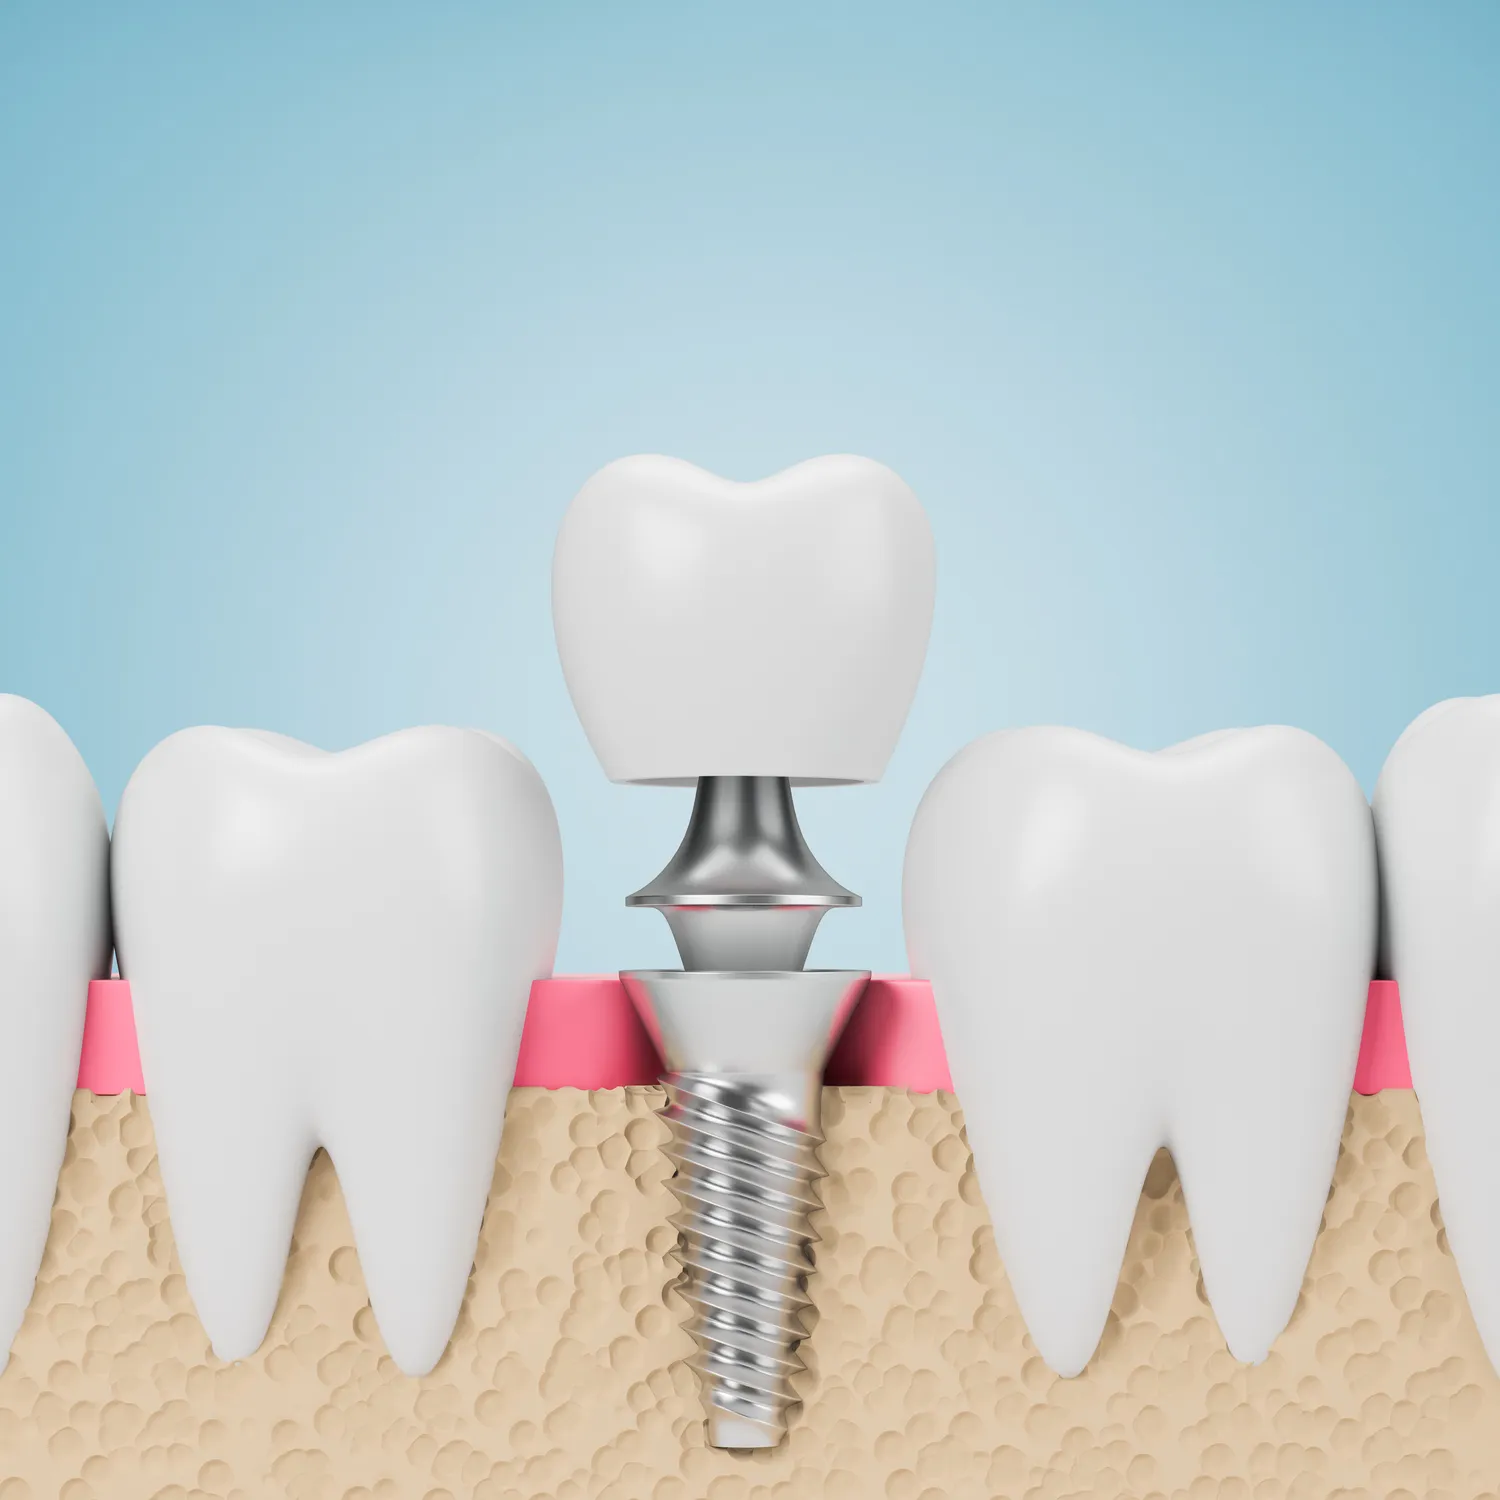

Stomatolog w Legnicy oferuje szeroki zakres usług, które są dostosowane do potrzeb pacjentów. Wśród najpopularniejszych zabiegów znajduje się profilaktyka, która obejmuje regularne przeglądy stomatologiczne oraz czyszczenie zębów. Dzięki tym zabiegom można skutecznie zapobiegać powstawaniu próchnicy i innych chorób jamy ustnej. Kolejnym ważnym obszarem działalności stomatologa jest leczenie zachowawcze, które polega na wypełnianiu ubytków, a także leczeniu kanałowym zębów. W przypadku bardziej skomplikowanych problemów, takich jak usunięcie zęba mądrości, stomatolog w Legnicy również dysponuje odpowiednimi umiejętnościami i narzędziami. Warto również wspomnieć o ortodoncji, która zajmuje się prostowaniem zębów i poprawą zgryzu. Stomatolodzy często współpracują z ortodontami, aby zapewnić pacjentom kompleksową opiekę. Dodatkowo, wiele gabinetów oferuje usługi estetyczne, takie jak wybielanie zębów czy zakładanie licówek, co pozwala na poprawę wyglądu uśmiechu. W Legnicy można znaleźć specjalistów zajmujących się implantologią, którzy pomagają w odbudowie brakujących zębów za pomocą nowoczesnych implantów.

Koszty usług stomatologicznych w Legnicy mogą się różnić w zależności od rodzaju zabiegu oraz standardu gabinetu. Warto zaznaczyć, że ceny są często konkurencyjne w porównaniu do innych miast w Polsce, co czyni stomatologię dostępną dla szerszego grona pacjentów. Podstawowe usługi, takie jak przegląd stomatologiczny czy czyszczenie zębów, są zazwyczaj dostępne w przystępnych cenach. Leczenie próchnicy, które obejmuje wypełnianie ubytków, również nie powinno nadmiernie obciążać budżetu pacjenta. Koszty mogą wzrosnąć w przypadku bardziej skomplikowanych zabiegów, takich jak leczenie kanałowe czy ekstrakcja zębów mądrości. Warto jednak pamiętać, że inwestycja w zdrowie jamy ustnej jest kluczowa dla ogólnego samopoczucia i jakości życia. Ceny usług ortodontycznych oraz implantologicznych mogą być wyższe, ale wiele gabinetów oferuje możliwość rozłożenia płatności na raty lub korzystania z programów lojalnościowych. Pacjenci powinni również zwrócić uwagę na dostępność ubezpieczeń zdrowotnych, które mogą pokrywać część kosztów leczenia stomatologicznego.